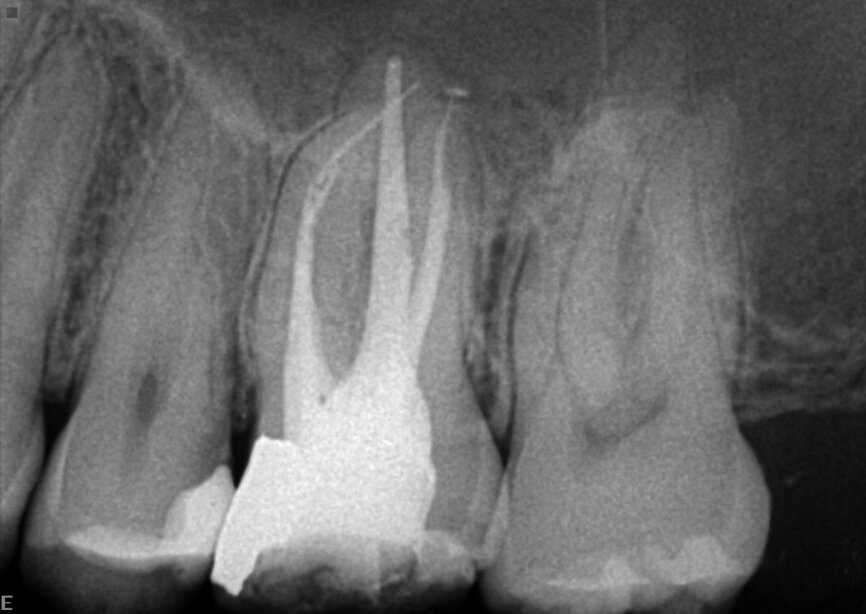

Le patient avait été adressé au cabinetpour une douleur sourde qui affectait une molaire supérieure. Sur la radiographie préopératoire, nous pouvions observer toute une série de matériaux d’obturation, notamment des mono-cônes, des colles composites et des cônes d’argent, dont certains étaient déjà fragmentés. L’un des fragments dépassait de la racine. Après un examen minutieux du sinus et de la membrane, nous avons pu constater que celle-ci avait été perforée en raison du processus inflammatoire et de l’infection qui avait provoqué une sinusite (Fig. 15).

J’ai pratiqué l’intervention sous un microscope opératoire et ai utilisé des inserts ultrasoniques et des limes rotatives K3 XF (Kerr Dental), pour extraire tous les anciens matériaux d’obturation du système canalaire. J’y ai alors inséré un tampon de ouate sec et place un ciment provisoire, car le patient se sentait fatigué après cette longue séance de traitement (Fig. 16). La figure 17 montre quelques débris mineurs des cônes d’argent qui avaient migré au-delà de l’apex radiculaire mésiale. J’ai pu extraire un petit morceau du cône d’argent au moyen de la macro canule du système Endovac et effectuer un nettoyage chimique du système canalaire.

La figure 18 montre la situation immédiatement après l’intervention, en particulier l’obturation des canaux mésiaux. Il est possible d’observer une légère amélioration de la membrane de Schneider et du sinus. La figure 19 a été prise au cours de la visite de suivi a trois mois et montre une fermeture presque complète de la membrane et de l’os du plancher sinusien.